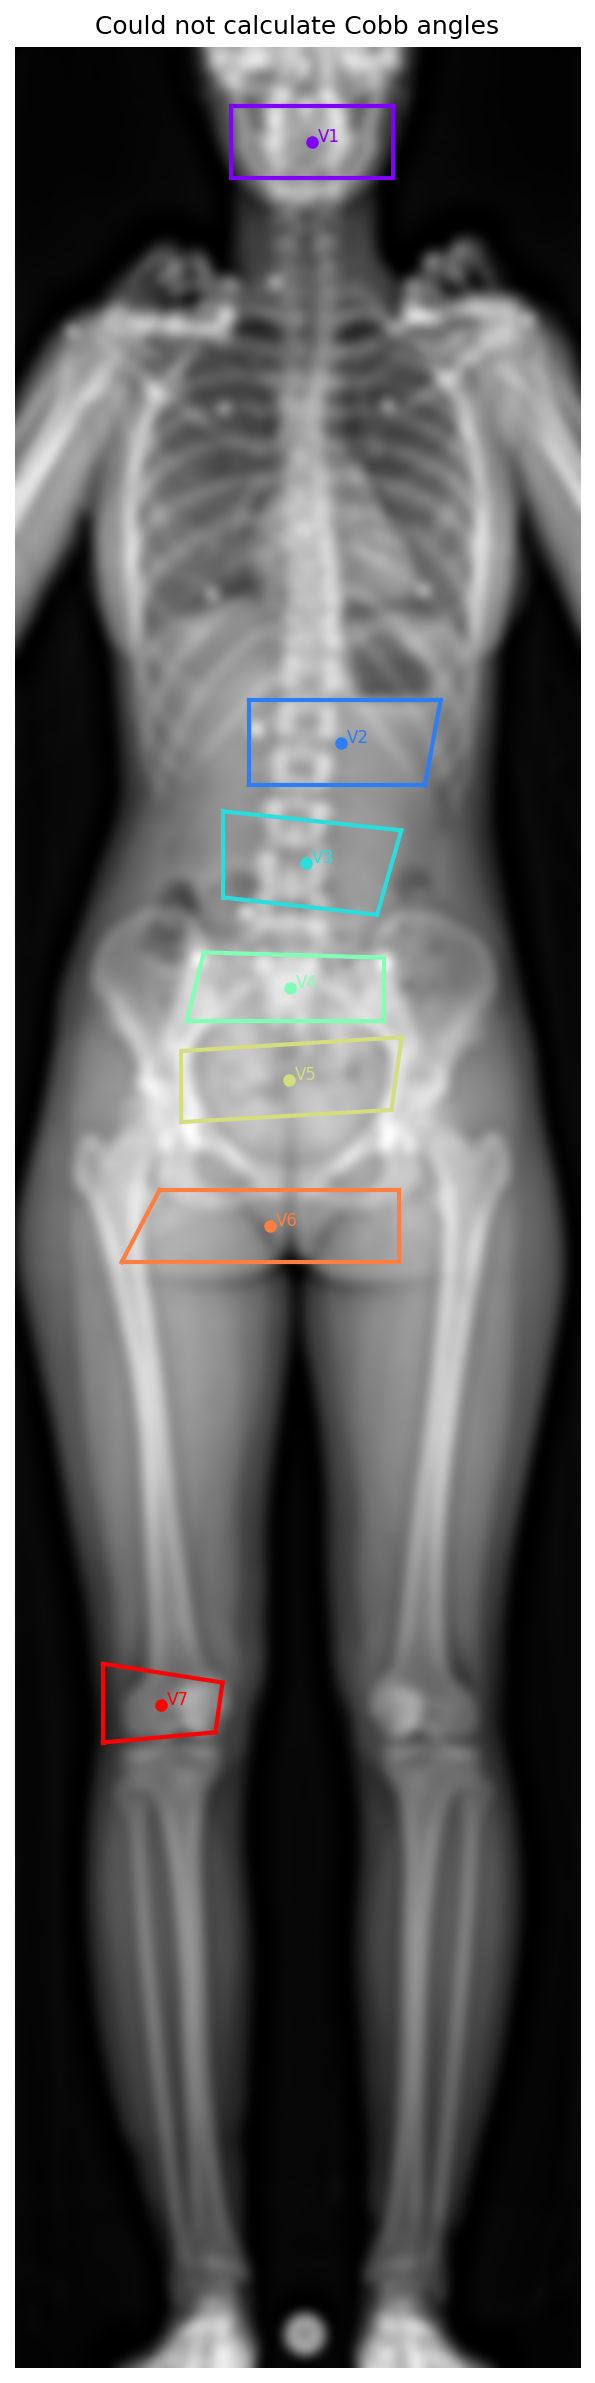

braceiqmed/scoliovis-api/balgrist_results/patient12_patient12_ap_result.png